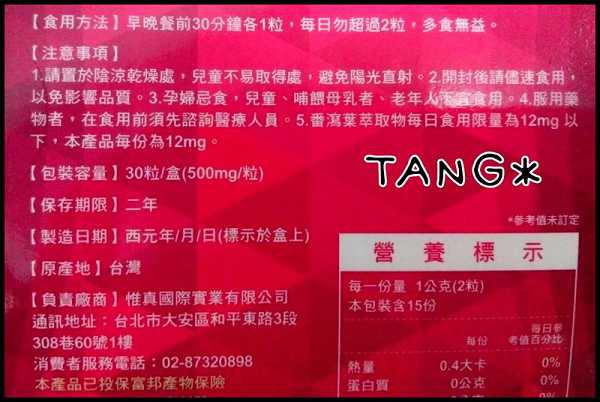

Supercut塑魔纖立塑膠囊的成分有:瓜拿那萃取粉、肉桂萃取粉、辣椒萃取物(唐辛子)、吡啶甲酸鉻、番瀉葉粉末、玉米澱粉、氧化鎂、二氧化矽。

食用方式:早晚餐前30分鐘各1粒,每日不超過2粒。(多食無益)

番瀉葉萃取物每日食用限量為12mg以下,